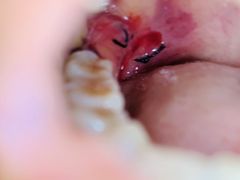

• -华中科技大学同济医学院附属同济医院(汉口院区)

匿名用户 | 21-07-04

报错